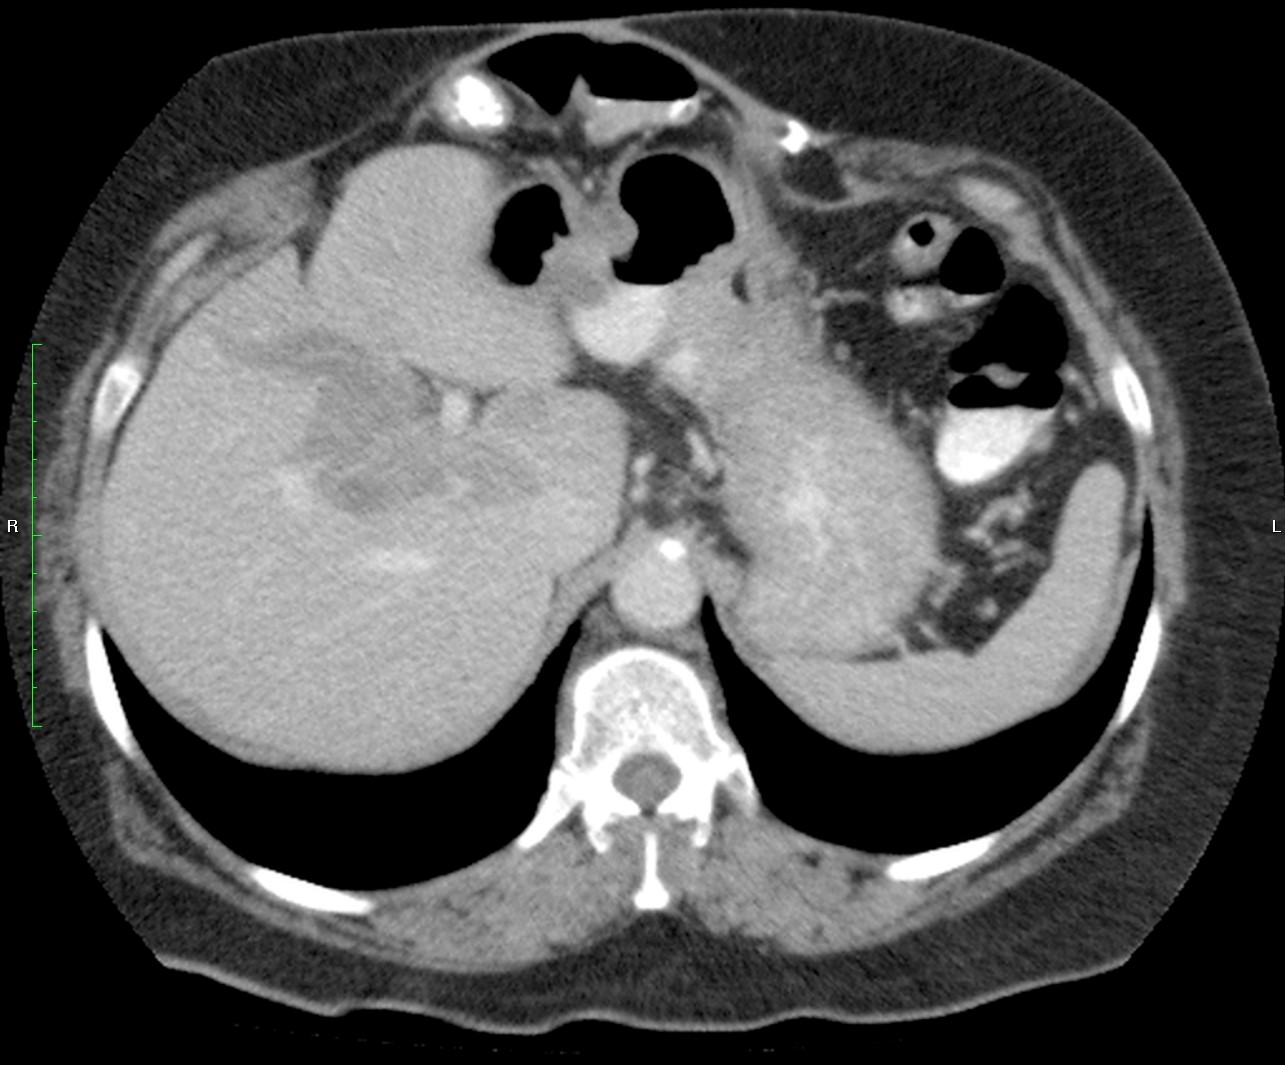

Mujer de 57 años.

Cuadro clínico de 1 mes de evolución caracterizado por distensión abdominal e hiporexia.